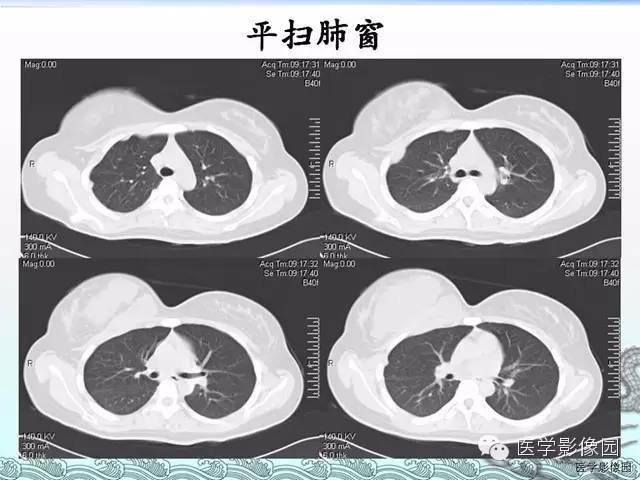

胸壁结核1例影像表现

【病例】胸壁结核1例影像表现